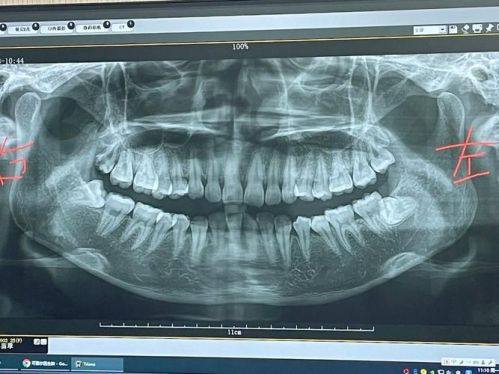

18. 口腔全景片:100 - 300元

19. 口腔CT:300 - 800元